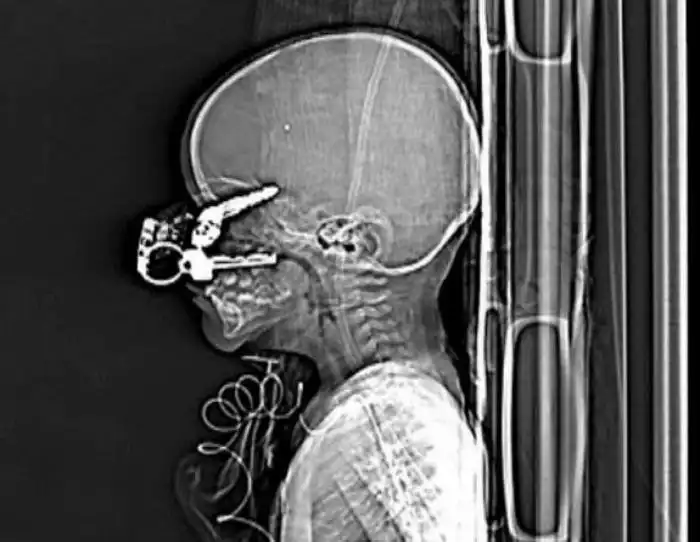

Необычные предметы в теле людей на рентгеновских снимках

На рентгеновских снимках людей порой можно обнаружить самые необычные предметы, которые находятся в их теле.